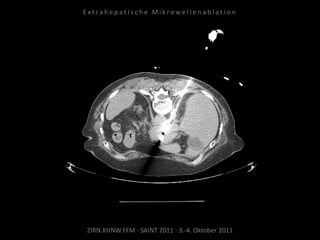

Bildgebung vor MWA:

CT vom 14.07.2010

Metastase lateral der linken Niere

nahe Colon descendens progredient.

Situation:

Metastasierung über längeren Zeitraum

lokal begrenzt,

1 Metastase progredient.

Organnahe Lage in unmittelbarer

Nachbarschaft zur linken Niere bzw. zum

Colon descendens.